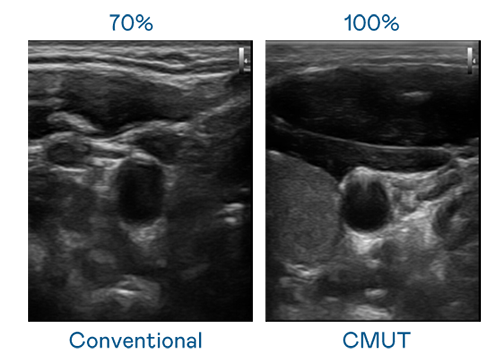

CMUT 技术是一种用电容式微机电元件来产生超音波讯号的技术。与传统 PZT 压电式技术相比,CMUT 频宽增加 30%,更宽频的超音波讯号让影像解析度大幅提升,是实现高影像品质医疗超音波扫描、促进精准医疗发展的关键技术。

超音波影像的解析度高低,首先取决于探头能发出的讯号频宽。豪门国际 CMUT 可提供高清晰的超音波讯号,提供高频宽、高灵敏度、影像纹理细节更高的超音波影像,协助医护人员缩短影像判读时间及利用精准的医疗影像进行诊断。